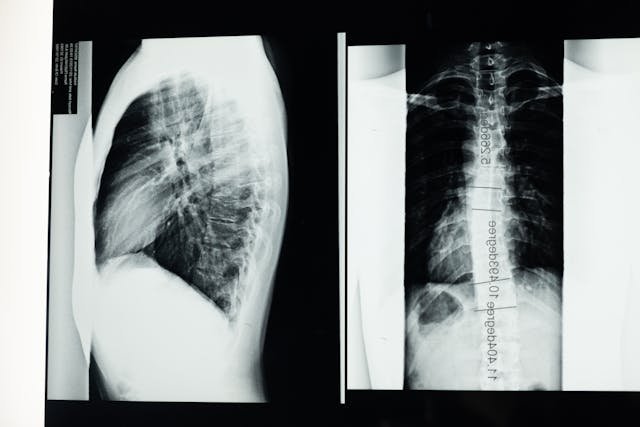

Preparing for Spine Surgery

For a spine operation to be effective, planning is essential. Start with preoperative consultations and assessments to determine your general state of health. Imaging and diagnostic procedures like CT or MRI scans aid in identifying the problem. Adhere closely to any preoperative instructions given, including any fasting, medication adjustments, and lifestyle modifications. It’s also crucial to mentally and emotionally prepare; knowing what to expect helps you stay upbeat and minimize nervousness. You can feel more at ease by sharing your worries with your surgeon and your loved ones. Additionally, make sure to consult a reputable surgeon with relevant experience and education. If you’re looking for the best spine surgeon in Arizona, consider researching top-rated specialists in that region. You improve your chances of a successful operation and recovery by being well-prepared.